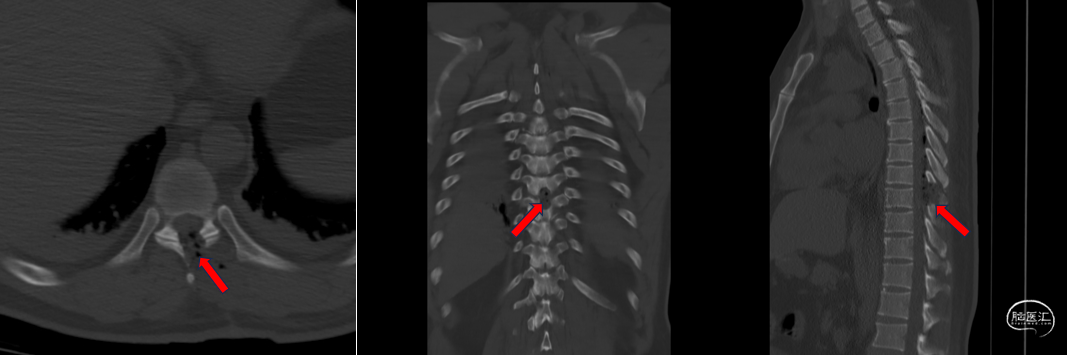

术后检查(胸椎CT重建):

![]()

诊疗计划

术前诊断:椎管内占位性病变(胸9节段,神经鞘瘤?)

手术计划:显微镜微通道下椎管内肿瘤切除术。

手术经过:手术过程:全麻后俯卧位,安置电生理探针,C臂定位,设计手术切口为胸9棘突左侧中线旁2cm直线切口,长度约2cm,切开到皮下,止血,于肌间隙置入定位针,再次定位确认,置入套管逐级扩张,置入通道并固定,显微镜下切除棘突椎板表面筋膜,磨除棘突根部及椎板部分,咬除黄韧带显露硬脊膜囊,切开硬脊膜并悬吊,探查见肿瘤,瘤内减压后分离肿瘤,电凝并切断载瘤神经后取出肿瘤。严密缝合硬脊膜,缝合切口。